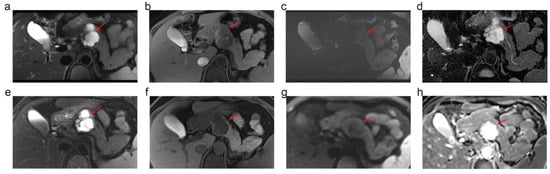

3.3. Depiction of PCL Imaging Features: 5.0 T vs. 3.0 T vs. MDCT